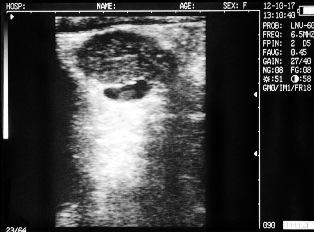

Ultrasound images of cows reproductive system, generated by a scanner Sonovet with rectal linear transducer.

Corpus luteum in the ovary of the cow